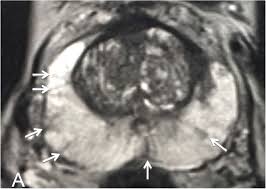

Transitional Zone Prostate Cancer Mri - Multi Parametric Mr Imaging Of Transition Zone Prostate Cancer Imaging Features Detection And Staging / Here are 10 more facts about prostate cancer.

Https Epad Uroweb Org Wp Content Uploads 3 Role Of Mri J Barentsz Pdf

Https Epad Uroweb Org Wp Content Uploads 3 Role Of Mri J Barentsz Pdf from